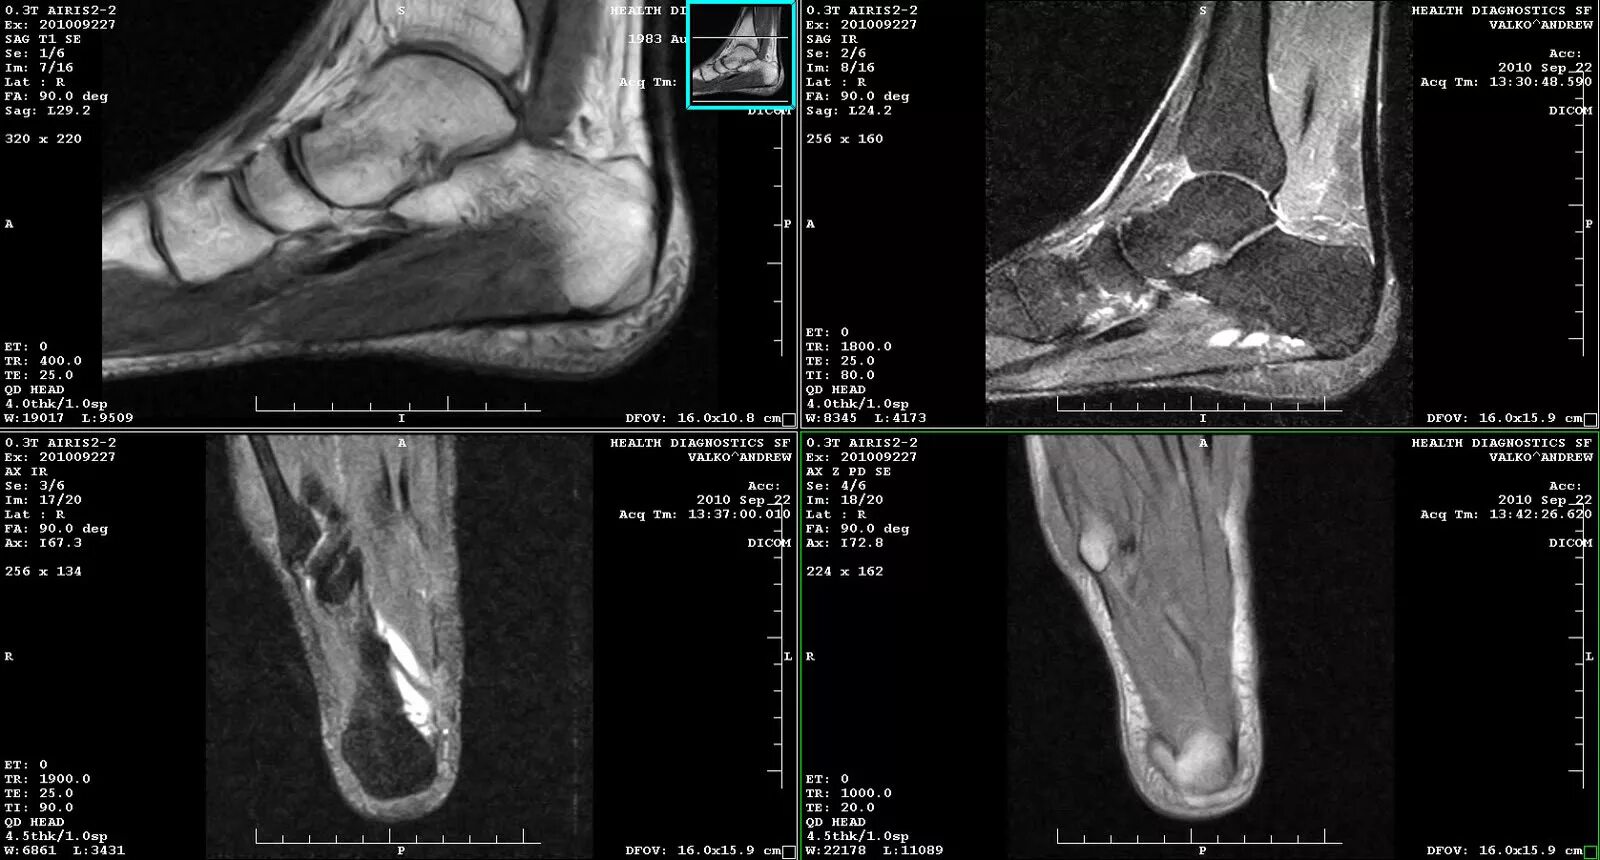

Кт суставов что показывает